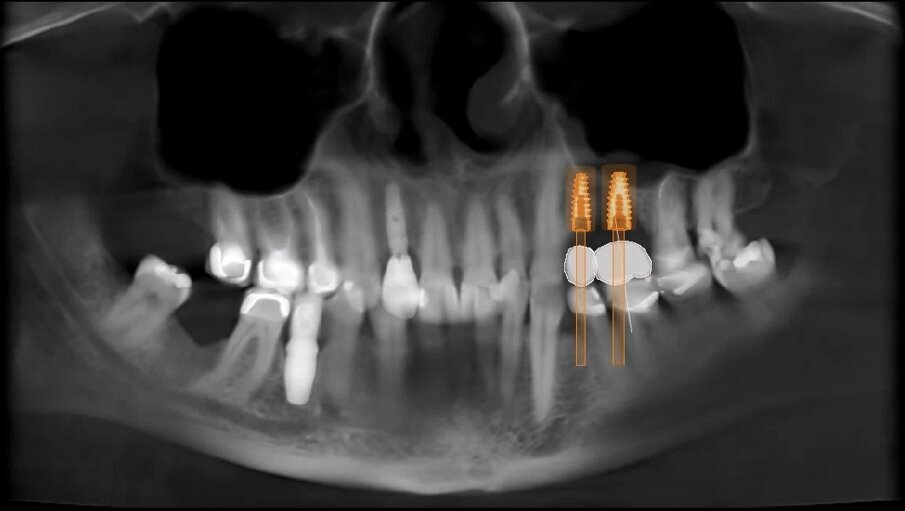

Fig. 10_Pianificazione finale in visione Panorex.

Appare quindi chiaro come eseguire una valutazione pre-operatoria in ambiente digitale ci permetta di prendere in esame una grande quantità di parametri che in passato erano lasciati alla sensibilità ed all’esperienza dell’operatore (Fig. 10). Eseguire questo tipo di valutazione tuttavia non è affatto complesso, oggi per la pianificazione di un caso di elevazione del seno mascellare è già gold standard richiedere una CBCT dell’arcata dentale superiore estesa al COM e gli unici step da aggiungere sono: il rilevamento di una scansione digitale intra-orale (o impronta analogica tradizionale che verrebbe acquisita e digitalizzata in laboratorio) e la realizzazione di una ceratura diagnostica virtuale con l’obiettivo di accoppiare queste informazioni con il dato radiologico CBCT all’interno di un software specifico che consenta la progettazione del caso. Sfruttando tali strumenti possiamo essere quindi in grado di fornire ai nostri pazienti risultati più predicibili ed inoltre evidenziare, prima di iniziare il trattamento, eventuali criticità avendo margine temporale e progettuale per correggerle.